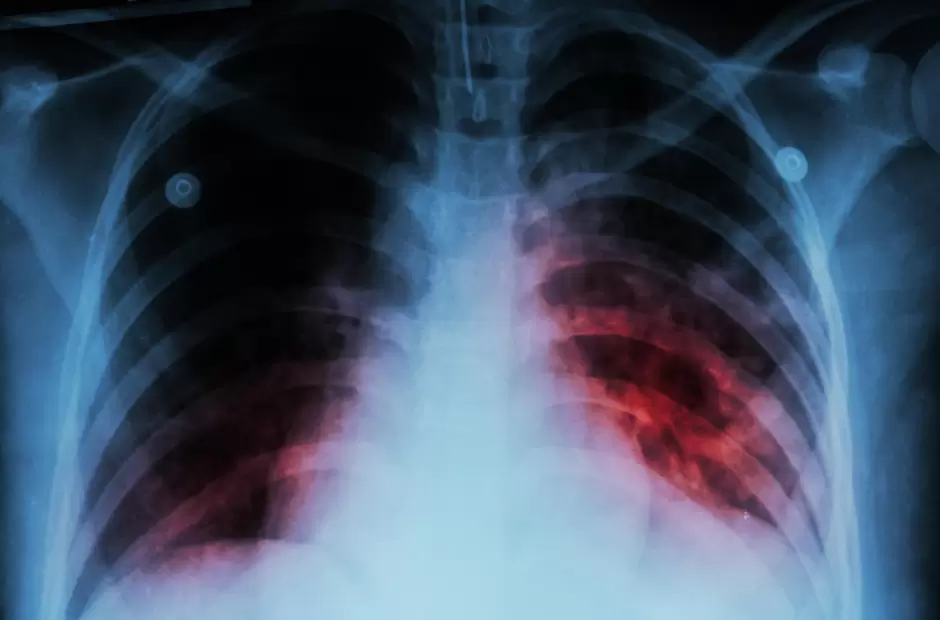

Importante: científicas argentinas desarrollan una fórmula pediátrica contra la tuberculosis

El medicamento es un jarabe saborizado que incluye tres fármacos indicados. En el mundo casi no existen presentaciones comerciales de este tipo. La enfermedad afecta a más de 10 mil argentinos todos los años y el 17% son menores de edad.

Aunque parece una enfermedad de otro siglo, la tuberculosis sigue enfermando a los argentinos. En 2020 se reportaron más de 10 mil casos y 656 muertes (17 por ciento niños y adolescentes) según el Ministerio de Salud de la Nación. Su tratamiento es complejo porque requiere administrar tres fármacos y por varios meses En la población pediátrica el problema es mayor porque no hay formulaciones específicas.